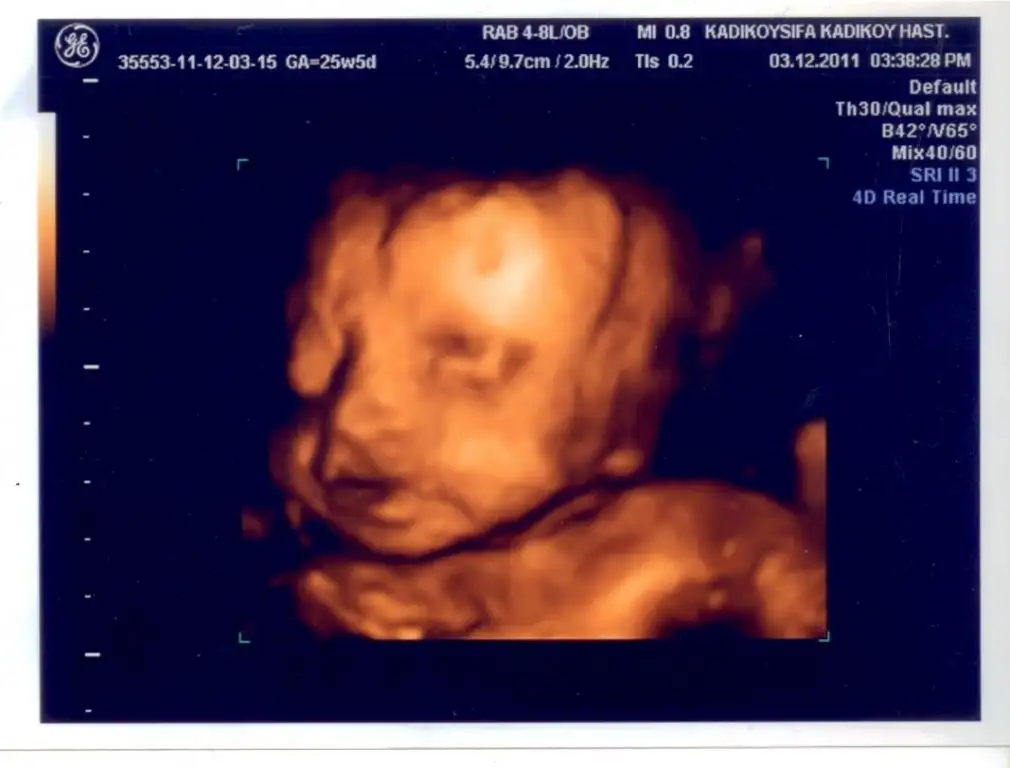

TEYZELERİİİ SÜPPRRİİSSSSSSSSSSSSSSSSSSSSS

MAŞALLAH ALLAH NAZARLARDAN SAKLASIN ÇİRKİN OĞLAN DİYELİMDE NAZAR DEĞMESİN (BENİM ANNEM BEBEKLERİ ÇİRKİN DİYE SEVİYO BU YÜZDEN :) )

canım maşallah ya ne güzel yüzünü göstermiş oğluşun. çok fotojenik olacak ben söyliyim sana. bizimki yüzünü hep saklıyor...

çok güzel fotonuz...

maşallahhhhh kuzucugaaaaa Allahım nazarlardan esirgesin inş.....

oyyyyyy maşallah allah nazarlardan saklasın benim kızım gibi poz vermeye çok meraklı senin şehzaden

ilk defa böyle poz veriyo:))) kıçını dönüyodu normalde:))) bizde şaşırdık busefer..:))

Ayçacım çirkin oğluna 41 kere maşallah.bu kadar büyüdülermi yav:)

ayy canım yaa maşaAllah tosuncuğunagünaydınn kızlarr...yaw bizde 28+4 görünüyo dünkü usg de:) ben biraz daha kasarsam zaten haftaya çıkarıcam oğlanı:))

ay maşaAllah canım yaa, bu fotoları bile görünce içim bir hoş oluyor, Rabbim hayırla, sağlıcakla kucağına almayı nasip etsin